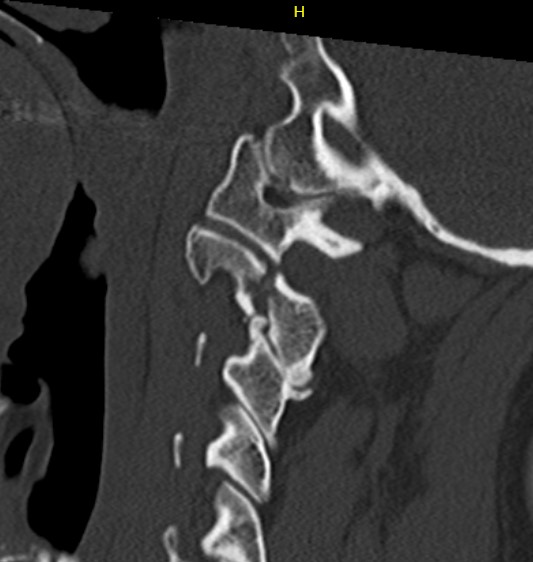

CT scan

Levine & Irving Classification

| Type | Characteristics | Mechanism | Management |

|---|---|---|---|

| Type I |

Vertical fracture line < 3 mm anterior displacement C2/3 disc normal |

Axial compression and hyperextension | Collar 6 weeks |

| Type II |

Vertical fracture line > 3 mm anterior displacement C2/3 disc disrupted Unstable |

Axial compression and hyperextension |

Traction and halo-vest Consider surgery |

| Type IIa |

Horizontal fracture line Significant angulation

|

Flexion-distraction |

Avoid traction Hyperextension and halo-vest Consider surgery |

| Type III | Type I with C2/3 facet dislocation | Surgery |